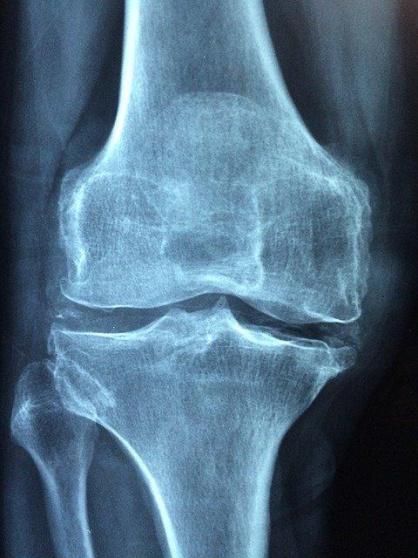

اكتشاف وسيلة لعلاج التهاب المفاصل الروماتيدي

وأفادت مجلة PNAS ، بأن مرض التهاب المفاصل الروماتيدي منتشرا على نطاق واسع. والأشخاص المصابون به يعانون طوال حياتهم من آلام دائمة ويصبحون قليلي الحركة. كما أن المصابين أكثر عرضة لأمراض القلب والكلى، ويعانون من ضعف البصر ومضاعفات أخرى. وقد ثبت أن هذا المرض يخفض العمر في المتوسط 3-12 سنة.